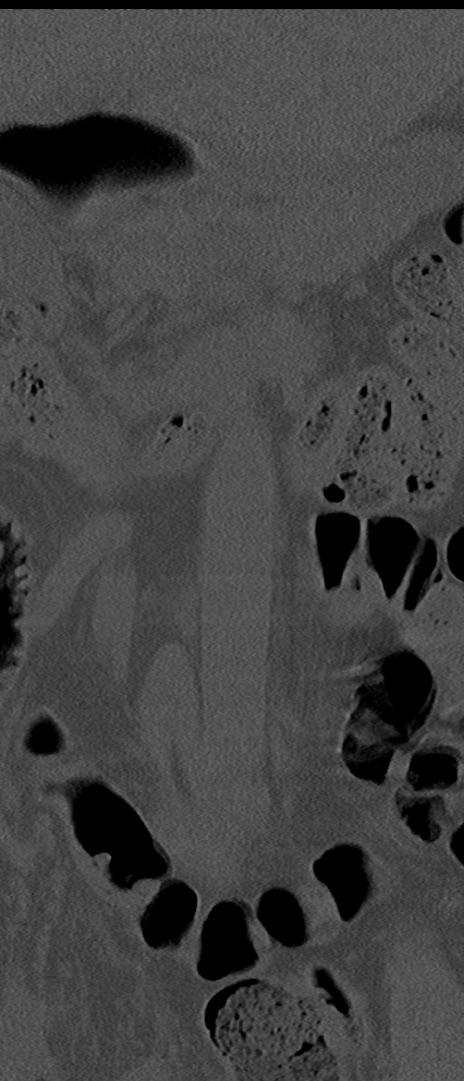

【整形】TIPS症例4 腰椎CT(冠状断像)

腰椎CT